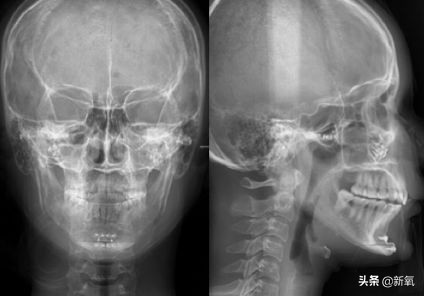

2015年9月,在更了解自家代理的医院和医生后,Jenny做了第二次轮廓手术,包括第二次颧骨手术、取出下巴的硅胶假体,以及V-line轮廓手术...

从头顶上来看,经过上次颧骨内推之后,她的颧骨两侧高低不一样,有些不对称,所以这次进行了修复矫正。

Vline手术的部分是把她的下巴切成T型,去掉中间的一部分骨头,再修剪骨头边缘,主要目的就是让脸小一点...

因为Jenny没有下巴,所以就在以上步骤的基础上,又把下巴再往前移动了一点,最后用钛钉固定。